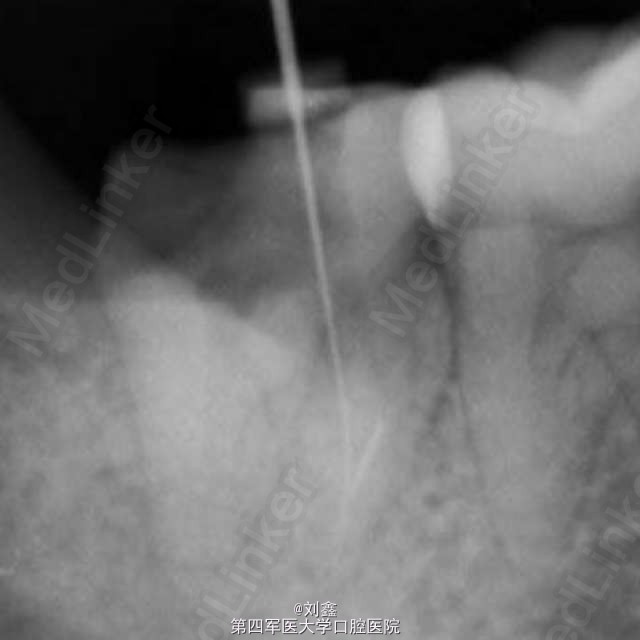

经典病例 根管内断针再治疗

患者女,29,右下后牙3年前于外院行治疗,冲填物脱落来我科。牙片示近中根有断针,遂行再治疗。

应用断针通过术治疗根管内器械分离